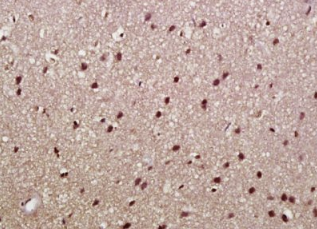

多聚甲醛固定,石蜡包埋(大鼠脑);用柠檬酸钠缓冲液(pH6.0)煮沸15min后获得抗原;用3%过氧化氢阻断内源过氧化物酶20分钟;阻断缓冲液(正常山羊血清)37℃30min;抗体(α-突触核蛋白)多克隆抗体在1:500下孵育。在4°C下过夜,然后用共轭二次进行20分钟的DAB染色。